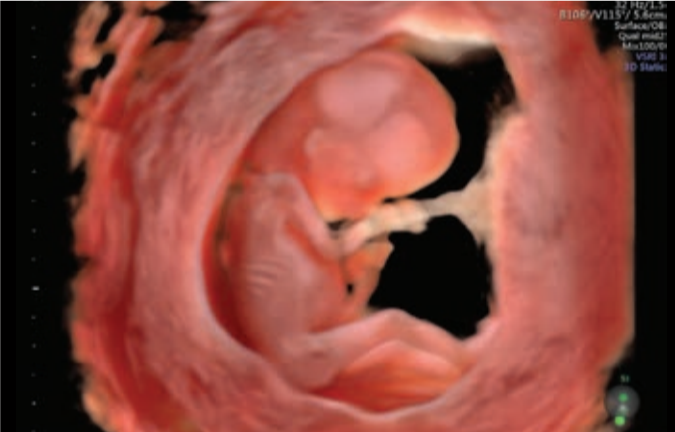

- Innovadora Arquitectura del Sistema Radiance para una calidad y precisión de imagen en 2D/3D/4D.

- Evaluar la salud fetal desde las etapas tempranas.